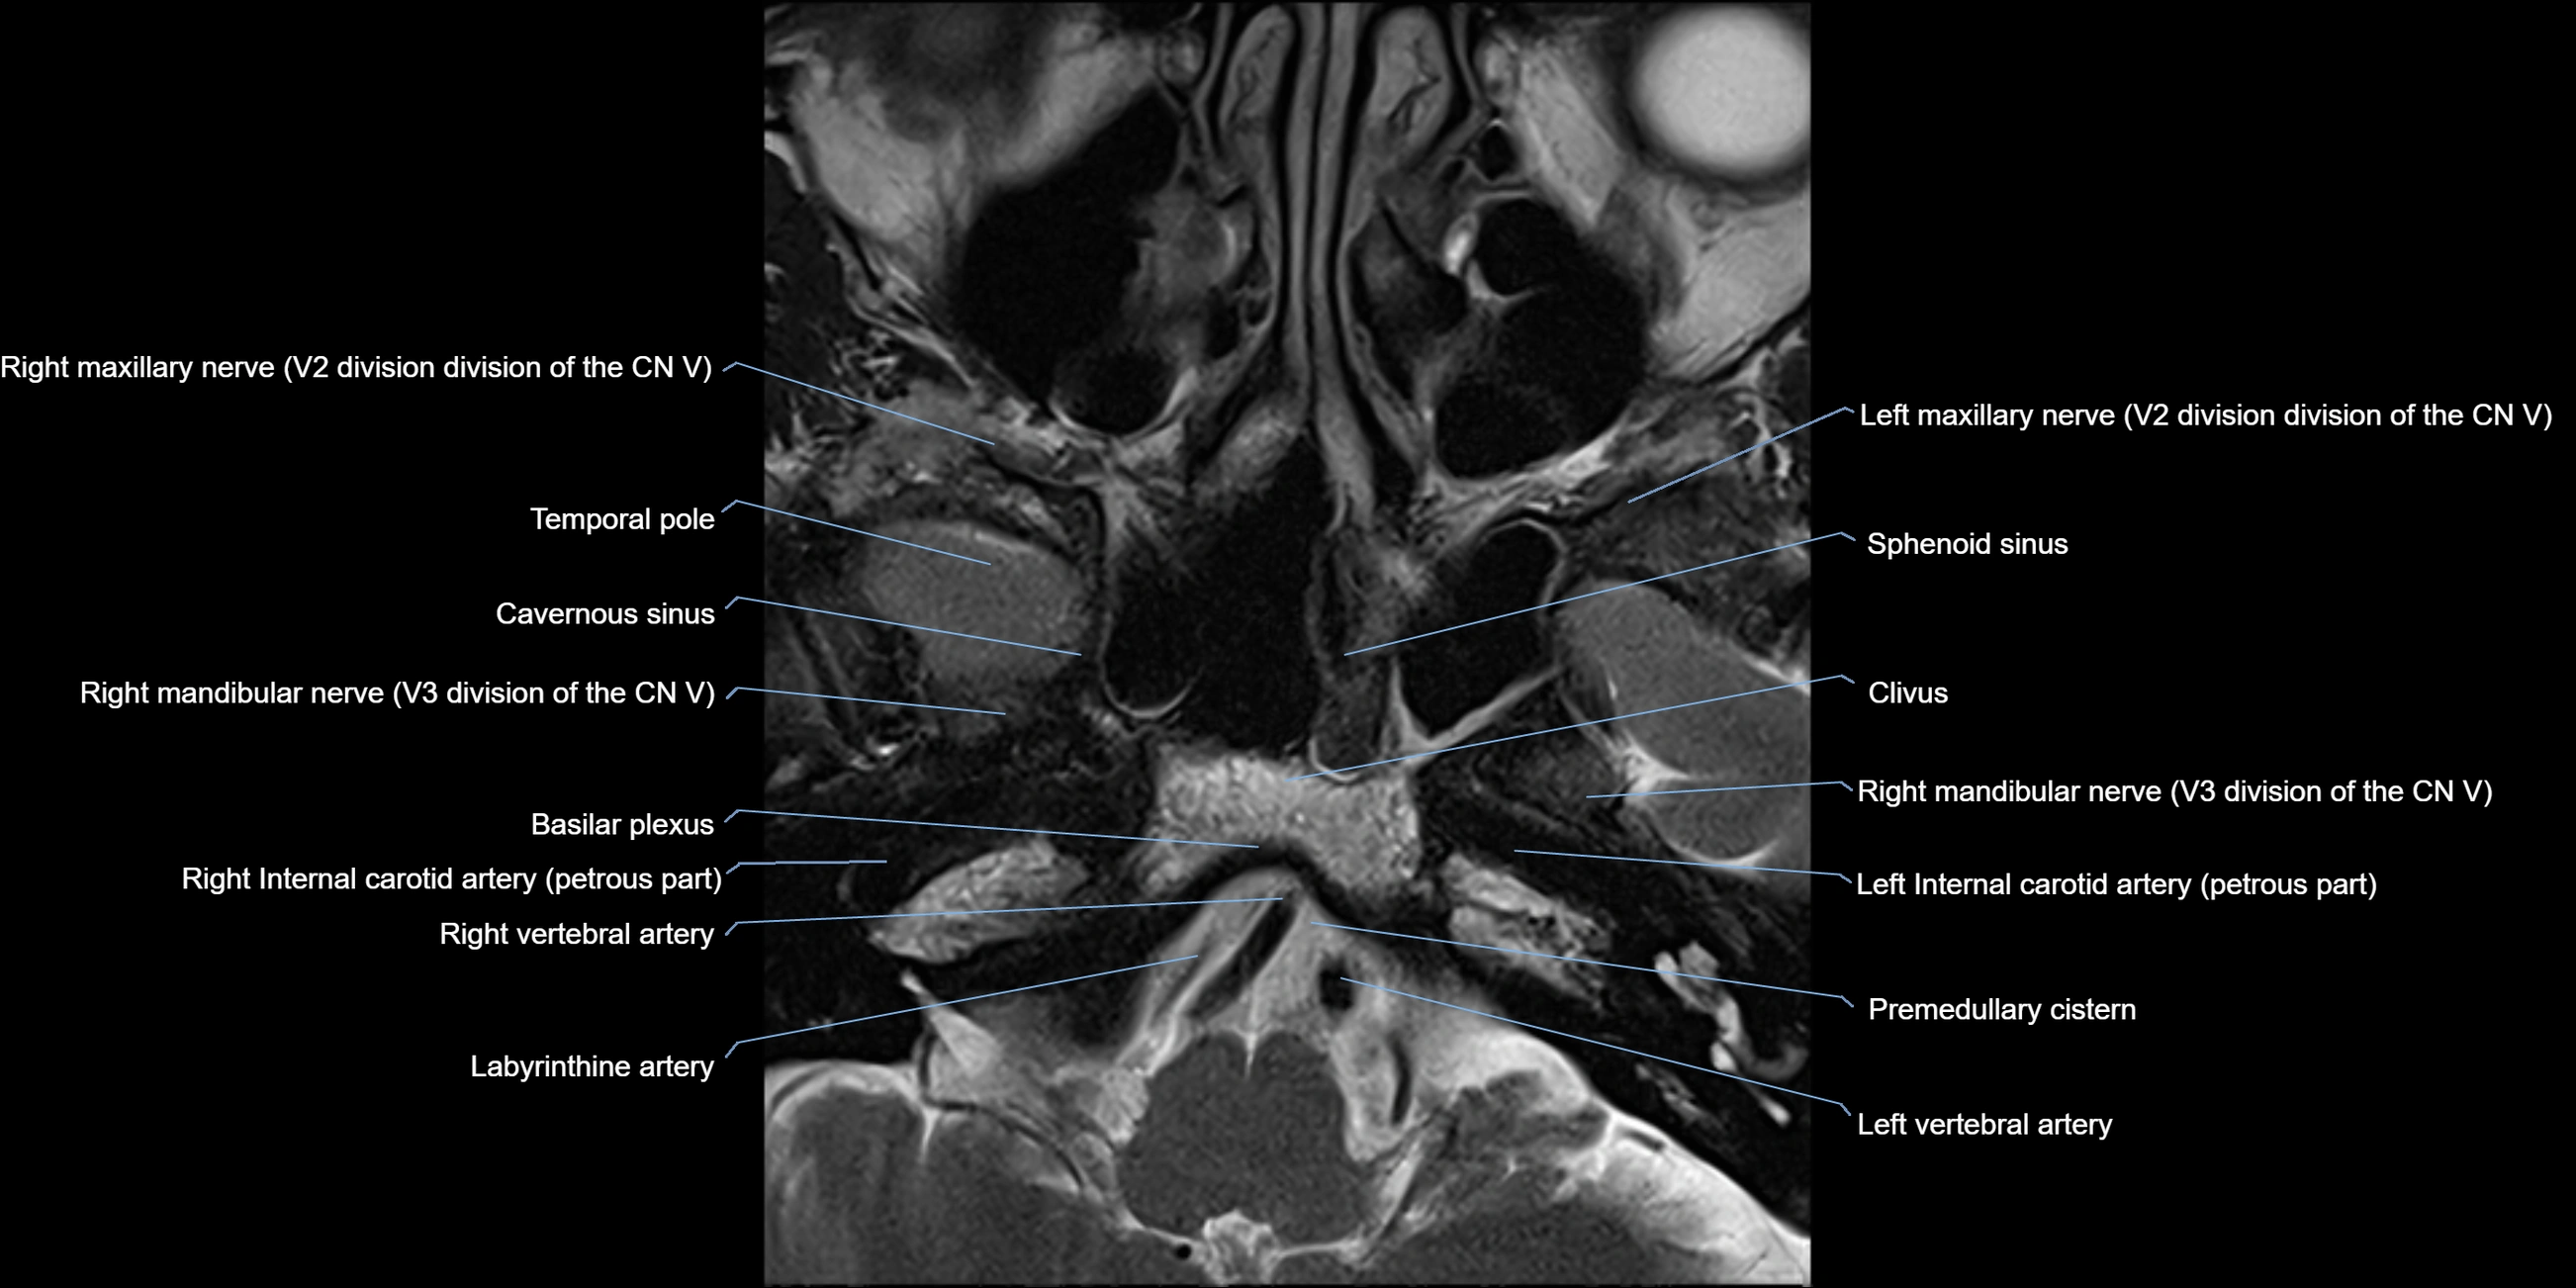

MRI Appearance

The abducens nerve is a small, thin, linear structure

Best visualized on high-resolution T2-weighted 3D MRI sequences (e.g., FIESTA or CISS)

Seen as a hypointense (dark) line running from the brainstem at the pontomedullary junction, traversing the prepontine cistern, and entering Dorello’s canal under the petrosphenoidal ligament, then into the cavernous sinus, and finally the orbit

May be challenging to visualize in standard MRI due to its small size

Pathology may be inferred by absence, displacement, or enhancement of the nerve